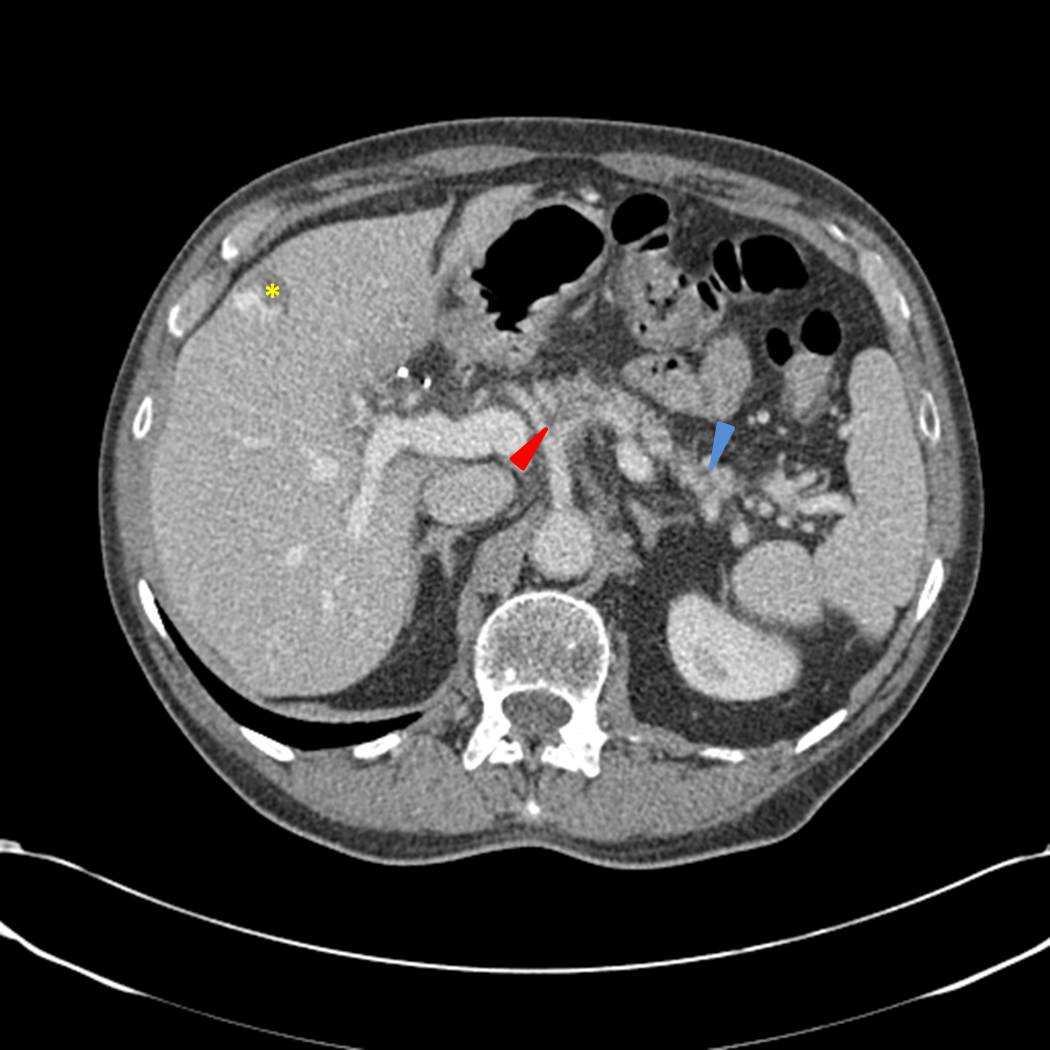

This abdominal ct scan shows tumor masses (malignant lymphomas) in the area behind the peritoneal cavity (retroperitoneal space). An abdominal mass is a lump felt in your tummy (abdomen). They discovered a mass in his abdomen. Keeping your cat indoors also helps protect them from getting into scrapes with other animals and health issues, including contagious diseases, fleas, ticks, and heartworms. Lymphoma can occur in the chest, causing coughing and labored breath.

Lump In Stomach Under Rib Cage - inantabosmika from 4.bp.blogspot.com However, these can be signs of many other illnesses as well. In this article, we talk about the causes, accompanying symptoms, and diagnosis of an abdominal mass. Stomach tumors are more prevalent in older animals, males, and. Some cats do not show any signs. They can include lethargy, loss of appetite, dehydration, weight loss, low body temperature, vomiting, jaundice, fever, and abdominal pain. This abdominal ct scan shows tumor masses (malignant lymphomas) in the area behind the peritoneal cavity (retroperitoneal space). It is a sarcoma arising from the lining of blood vessels; These 8 myths are not meant to offend anyone.

An abdominal mass is most often found during a routine physical exam. The differential diagnosis of a mass in the liver is broad but can be easily narrowed down based on two factors that are usually known at the time of. There are many different causes of an abdominal mass. In cases of metastasis to other body organs, prognosis is very poor, where survival may only be a few months. They are based on observations made over years of practice. And leiomyomas, adenomatous polyps, and adenomas (benign). This abdominal ct scan shows tumor masses (malignant lymphomas) in the area behind the peritoneal cavity (retroperitoneal space). The doctor is 99% sure that is is a malignancy. As fluid accumulates, it can also put pressure on the diaphragm, making breathing a challenge for those affected by the condition. Lymphoma can occur in the chest, causing coughing and labored breath. How long can cats live with stomach cancer? The cat is much more obviously ill than with simple retention of foetal membranes. In this article, we talk about the causes, accompanying symptoms, and diagnosis of an abdominal mass.